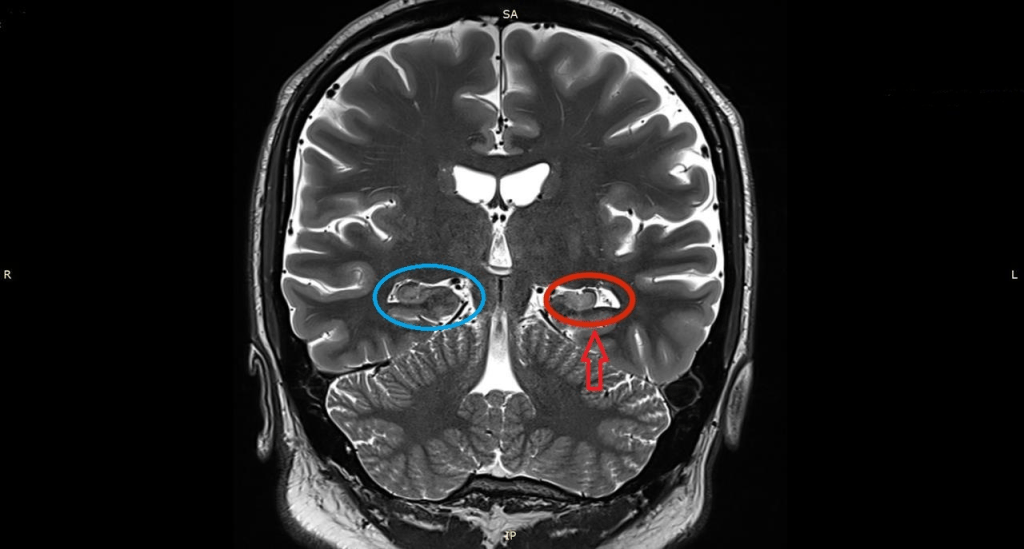

A closer look at my brain

I suffered a severe traumatic brain injury and was diagnosed with posttraumatic epilepsy early on in my recovery. Recently, however, I decided to see an epileptologist, or a neurologist who specializes in treating patients with epilepsy. Finding it weird that it never came to my mind to see an epileptologist, I decided to do so back in August of 2022 because I was having more frequent seizures. The doctor decided to order MRI scans of my brain; the MRI images showed left-sided MTS, and furthermore MTLE. One of the MRI images that shows the evidence of MTS is shown below.

The white tissue that the arrow is pointing to is scar tissue, indicative of left-sided MTS